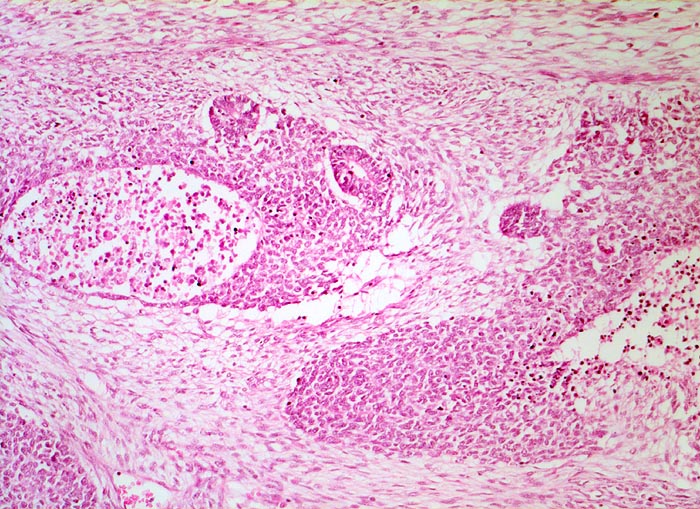

PathoPic – image database / PathoPic ID 5180 - Wilms-Tumor

Wilms-Tumor

Alle drei Komponenten des Wilms Tumors sind auf diesem Bild sichtbar. Das lockere spindelzellige Stroma, die zelldichte Blastemkomponente mit Nekrosen und Einschluss epithelialer Elemente in Form von Tubuli.

Graubrauner scharf begrenzter weicher Tumor mit fokalen Nekrosen und Einblutungen.